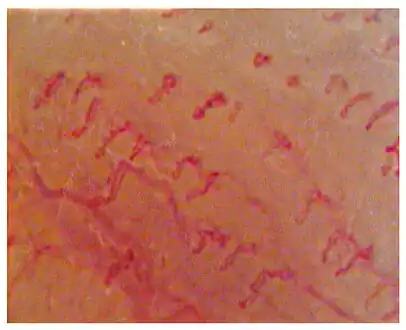

-

Capillaroscopic evaluation in Burning mouth syndrome -

Geographic tongue (benign migratory glossitis)